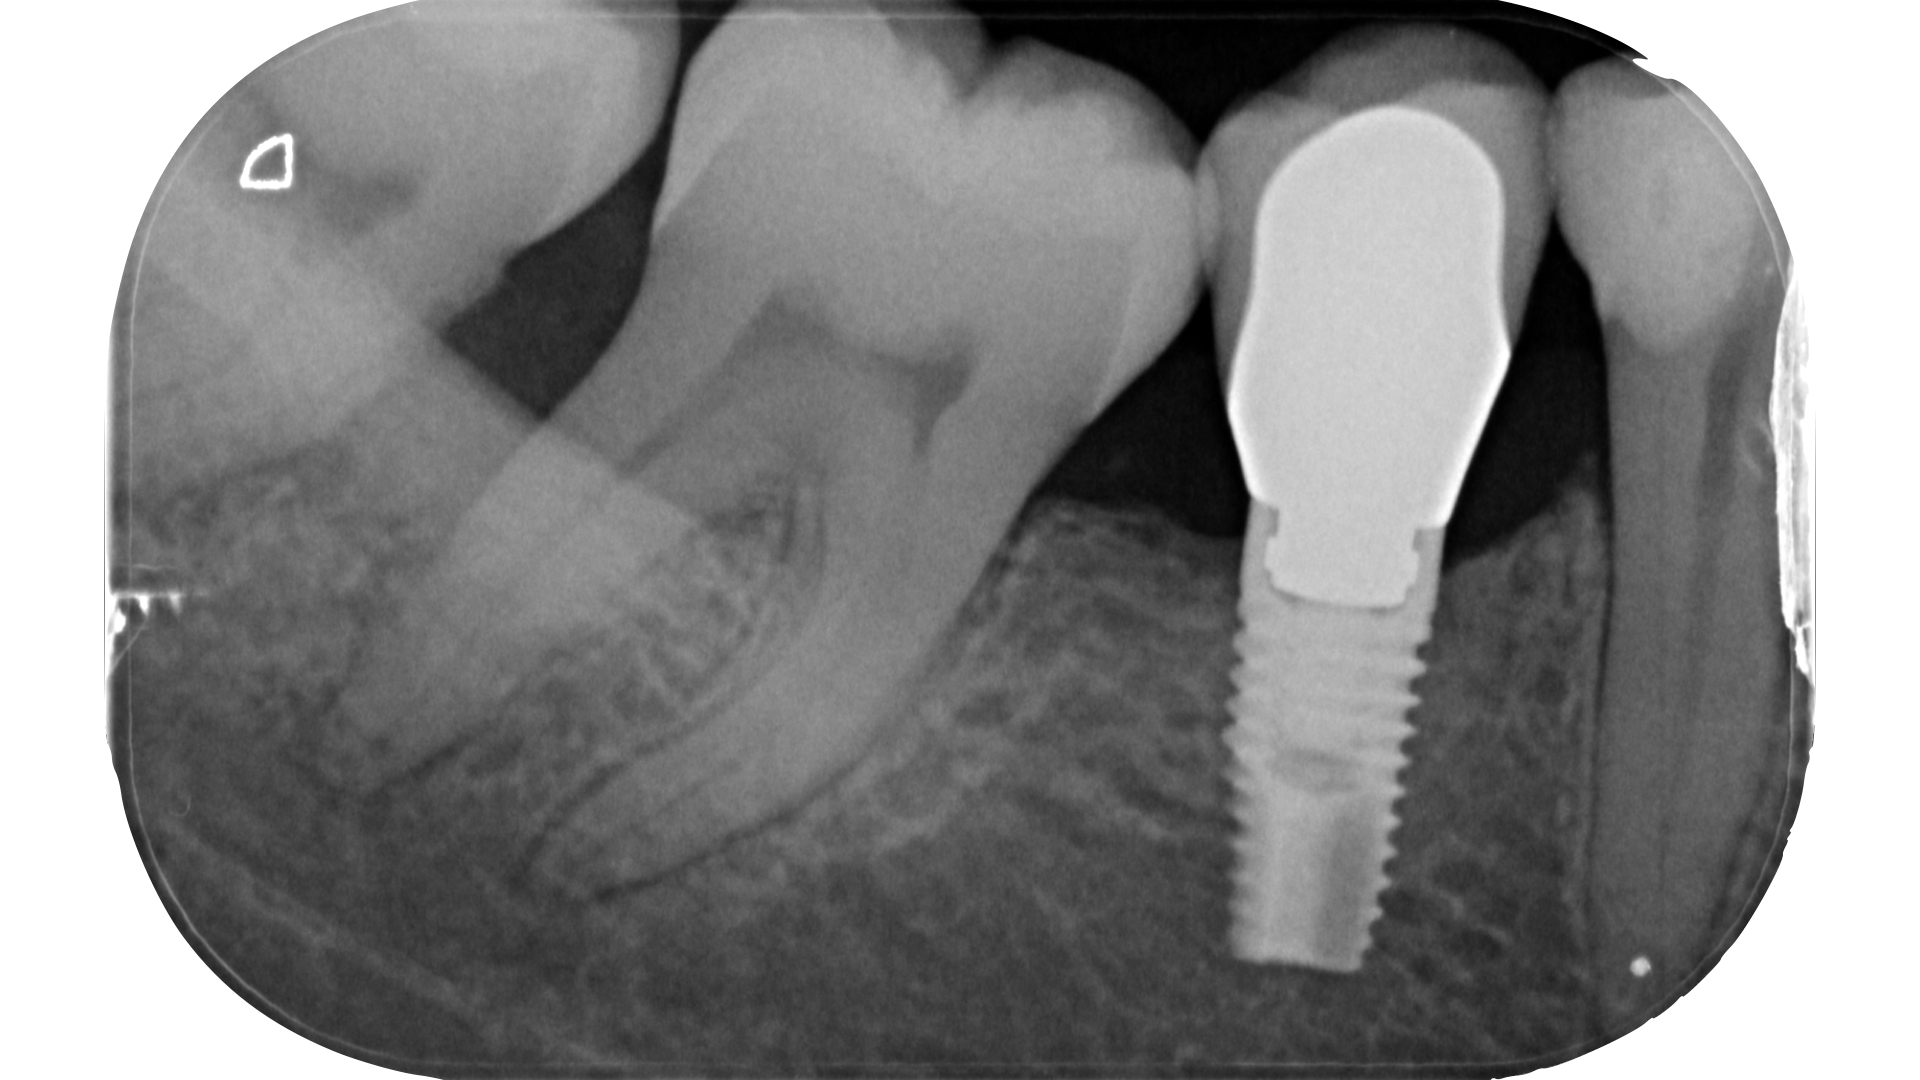

Devono essere valutate con molta attenzione la posizione dell’elemento in arcata e la sua inclinazione (Figure 6-7), l’entità e la posizione del processo carioso se presente, gli eventuali restauri posizionati sul dente e i rapporti con il parodonto: tutte queste considerazioni permetteranno al clinico di capire innanzitutto la mantenibilità e la possibilità di isolare mediante diga di gomma il dente. L’interpretazione degli esami radiografici consentirà inoltre di valutare alcuni parametri preoperatori di notevole importanza:

- presenza di radiotrasparenze periradicolari o periapicali;

- presenza di pregresse terapie canalari e valutazione della qualità delle stesse;